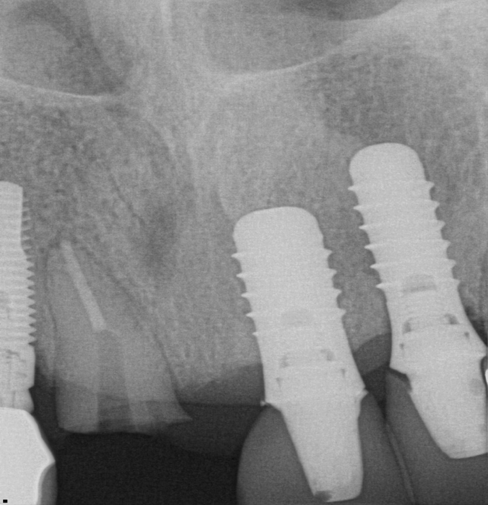

Fig 30. Preoperative periapical radiograph.

Figure 30

The next case follows the digital protocol for fully guided surgery and prosthetics. A CBCT radiograph, digital impression, and digital photography were the cornerstones to the success of this case. The 3D data set was electronically delivered to the dental laboratory. The data were merged and the process to develop the plan was initiated. The use of CBCT was essential in this case, particularly due to minimal space for placement of individual implants and single-unit crowns. The patient's chief concern was that she wanted to have single-unit crowns instead of fixed crown-and-bridge restorations because she was worried that she would someday find herself in an assisted-living facility; if that were to happen, she wondered, who would help floss under her bridge work? Her decision was to have single implants with individual crowns. CBCT technology is much more accurate in evaluating space maintenance and management.10 Periapicals in the past were rather close for calculating spacing; however, the CBCT identifies the buccal-lingual dimensions as well as the mesial-distal measurements. On review of the completed proposals for implant placement and provisionals, it was determined that there was sufficient spacing for implant placement to allow appropriate emergence profiles for the provisionals and then eventually the final single-unit cemented crowns. The proposal was accepted, and a 3D-printed surgical stent was fabricated, along with the PMMA provisionals (Figure 29 through Figure 35).

On the day of surgery, the plan was to extract teeth Nos. 21, 23, 24, 25, and 26, place 3.0 x 13-mm implants in the anterior region due to limited spacing, and place a 4.1 x 10-mm implant in the No. 21 extraction site. Before the extractions were performed, the No. 23 pontic was sectioned from the existing 2-unit cantilevered bridge utilizing ceramic and metal high speed rotary cutting burs ZR 6881 and H34L (Komet-USA), respectively. After removal of the pontic and extractions, the surgical guide was verified to be seating positively (Figure 36 through Figure 38). Surgical guide protocol was followed, and all implants were successfully placed and torqued to a value of greater than 35 Ncm (Figure 39 and Figure 40). All implants were placed without flapping, with the exception of No. 23. The flap was elevated to reposition lingual keratinized tissue facially for enhanced esthetic tissue profile. The implants were then prepared with a high-speed carbide bur (Komet-USA) with copious amounts of water (Figure 41 and Figure 42). The one-piece 3.0-mm diameter implant served the needs of the patient's spacing requirements. Inter-occlusal space requirements and path of draw were verified. The PMMA provisionals were air abraded and relined with crown-and-bridge material (Figure 43 through Figure 45).